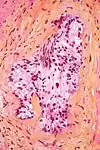

Micrograph showing a prostate cancer (conventional adenocarcinoma) with perineural invasion. H&E stain.

In pathology, perineural invasion, abbreviated PNI, refers to the invasion of cancer to the space surrounding a nerve. It is common in head and neck cancer, prostate cancer and colorectal cancer.